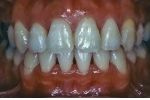

治療前後の比較

|